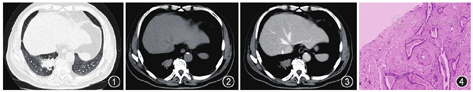

影像检查:胸部CT示右肺下叶后基底段见团块样占位(图1),大小约30 mm×40 mm,边界清楚,边缘不规则,密度均匀,CT值约43 HU(图2),增强后CT值约46 HU(图3),动脉期、门脉期、平衡期CT值分别为46、47、48 HU。

细胞学检查:刷检及灌洗液涂片均未见异常细胞。结核基因GeneXpert检测未检出。新型隐球菌荚膜抗原测定阴性。痰细菌培养及鉴定正常菌群生长;真菌培养7 d未见真菌生长。免疫组织化学染色:腺上皮细胞角蛋白7(CK7)、胃酶样天冬氨酸蛋白酶A(Napsin A)、甲状腺转录因子1(TTF1)、CK5/6、P63、P40均呈阳性,细胞膜增殖抗体Ki-67部分阳性,突触素(Syn)、CD56、嗜铬素(CgA)均呈阴性。于2019年1月7日行CT定位下右肺下叶肿物穿刺,病理表现:显微镜下见间质纤维黏液样组织增生伴红染絮状物沉积,其内见不规则腺管(图4),病理诊断:考虑肺淀粉样物质沉积症。

由于肺淀粉样物质沉积症是淀粉样蛋白在肺内的结节样积蓄,所以病灶内无血管供应,没有坏死区域,CT平扫密度均匀,增强扫描未见强化,这是该病例反映出的影像病理特征。本例病灶CT平扫显示右下肺占位,密度均匀,无典型胸膜凹陷、分叶征象,未见充气支气管征,增强后病灶无明显强化。近年来研究发现淀粉样变性损伤与局部细胞毒素,局部受体的相互作用和自由基损伤以及细胞凋亡机制有关[5,6],本例患者老年男性,并发痛风、糖尿病病史,可能与免疫力较低有关。